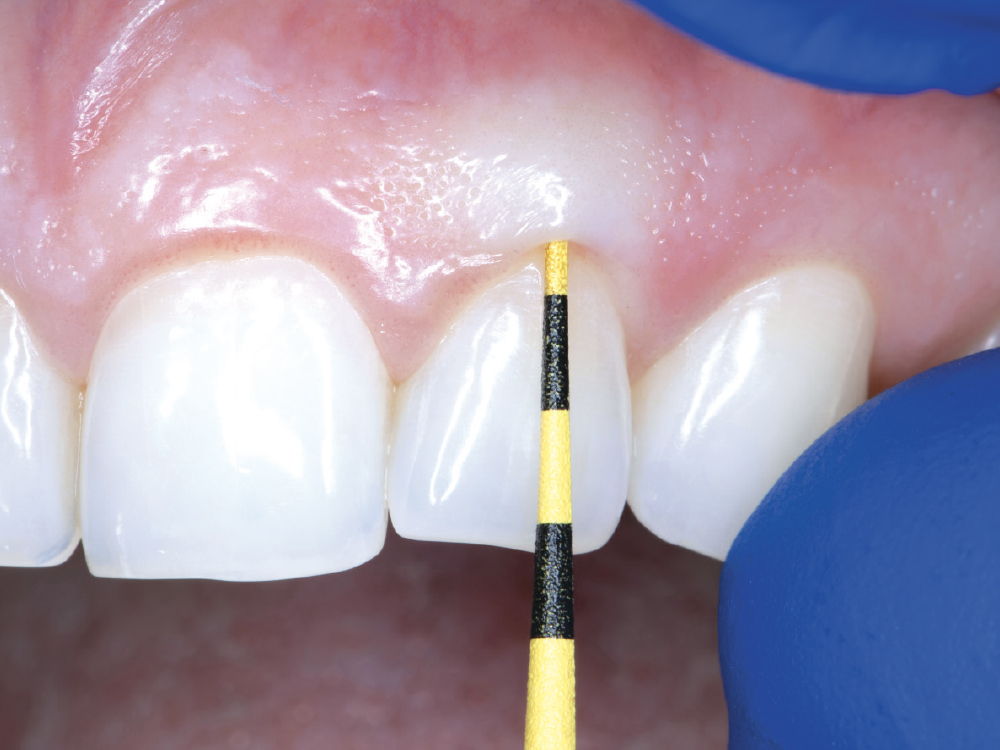

In the esthetic zone, assessing the gingival biotype helps identify the challenges associated with managing soft tissue.

Figure 4: In the esthetic zone, assessing the gingival biotype helps identify the challenges associated with managing soft tissue. As shown here, using a Colorvue® periodontal probe (Hu-Friedy MFG. CO., LLC; Chicago, IL) and observing the transparency of the soft tissue is an effective method for determining soft-tissue thickness. Thicker biotypes are typically more resistant to recession.  Fortunately, this patient had a thick gingival biotype, favoring the maintenance of the gingival architecture.